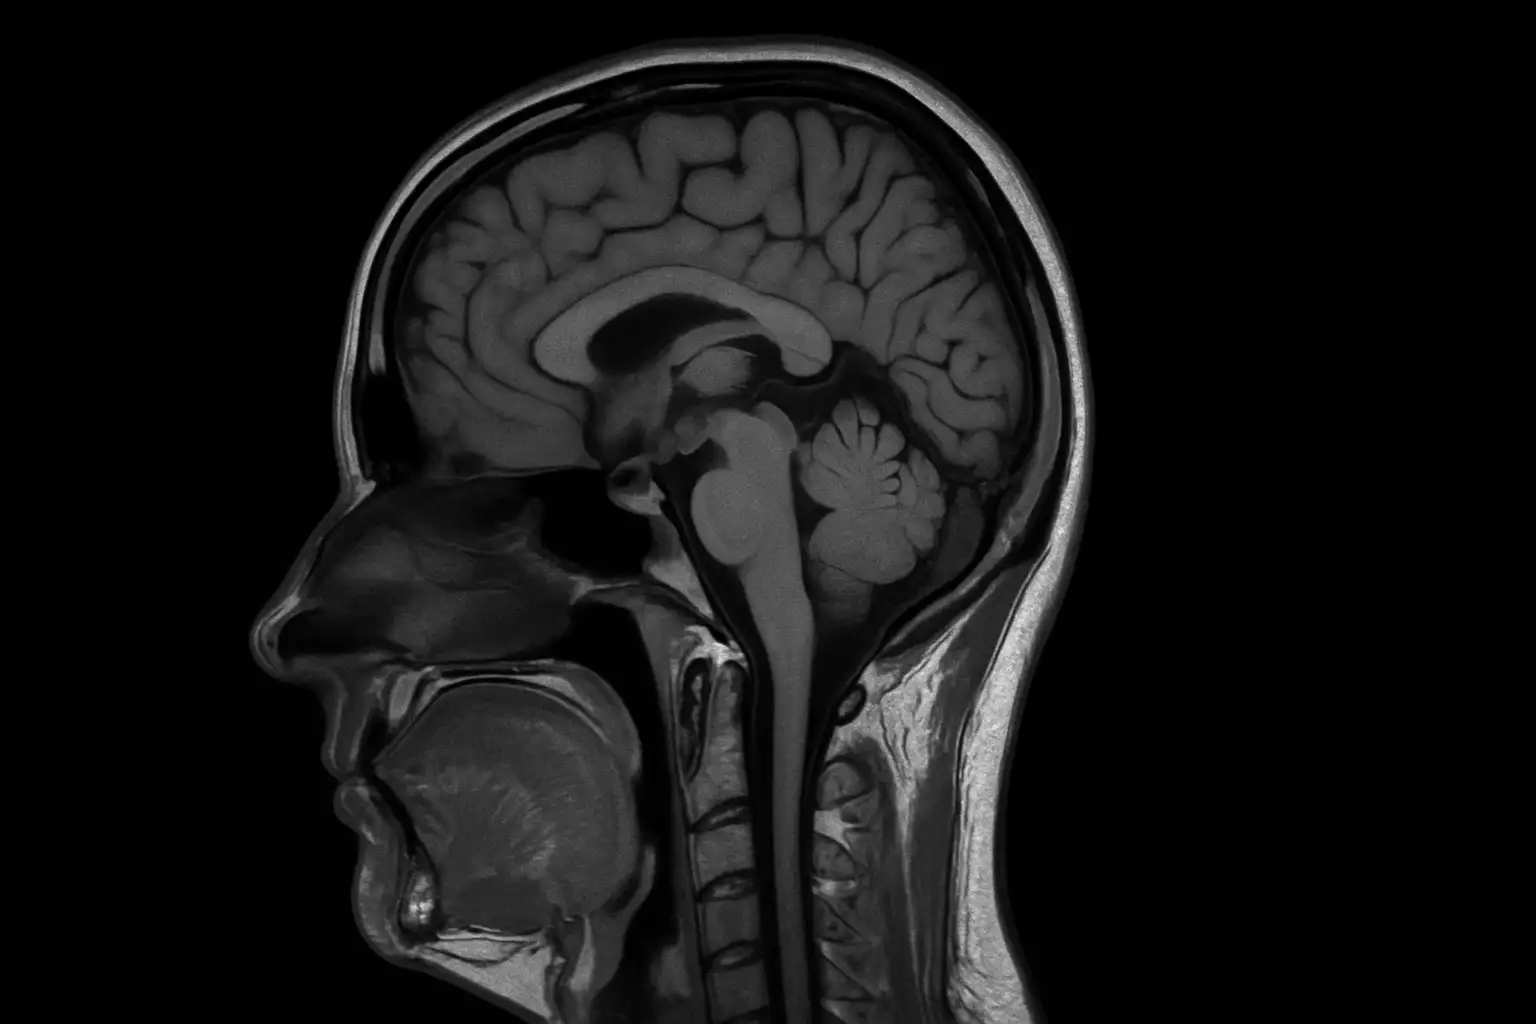

Магнитно-резонансная томография (МРТ) в медицинском центре «Бригид» использует современную технологию 1.5 Тесла для получения исключительно детальных изображений внутренних структур без ионизирующего излучения. Этот передовой метод визуализации обеспечивает непревзойденную контрастность мягких тканей, позволяя точно диагностировать неврологические, опорно-двигательные, абдоминальные и сосудистые заболевания с максимальным уровнем безопасности пациента.

Исключительная контрастность мягких тканей

Превосходная визуализация мозга, спинного мозга, мышц, связок и органов без ограничений контраста

Передовая нейровизуализация

Диффузионная, перфузионная, спектроскопическая и функциональная МРТ для комплексной неврологической оценки

Магнитно-резонансная томография (МРТ) — это неинвазивный диагностический метод, использующий мощные магнитные поля и радиоволны для создания детальных изображений органов и тканей. В отличие от КТ, МРТ не использует ионизирующее излучение, что делает её одним из самых безопасных методов визуализации. Напряженность магнита 1.5 Тесла обеспечивает оптимальный баланс между качеством изображения, скоростью сканирования и комфортом пациента.